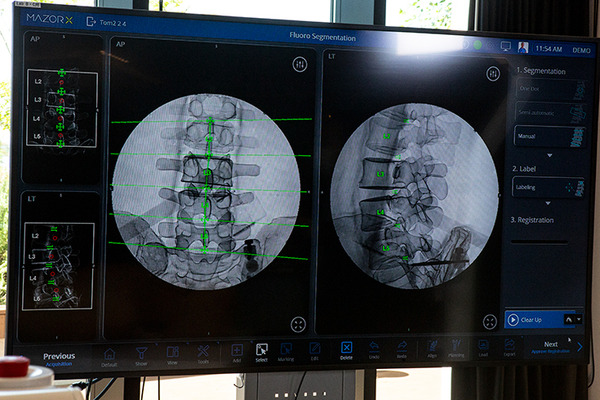

次に重要になるのは、手術室でうつ伏せに寝ている目の前の患者と、システム上にあるデジタルツインの3D患部データが全くズレることなく、同じ位置にあることを確認、デジタル用語でいうところの「キャリブレーション」を正確におこなう。X線撮影を行って、実際の患部と3D患部が全く同一の状態であることを確認する。

更に、X線撮影のような3D画像上にはリアルタイムで手術器具の位置情報や、挿入し始めたスクリューが表示できるので、挿入している状態や深さなどを確認しながら手術を行うことができる。